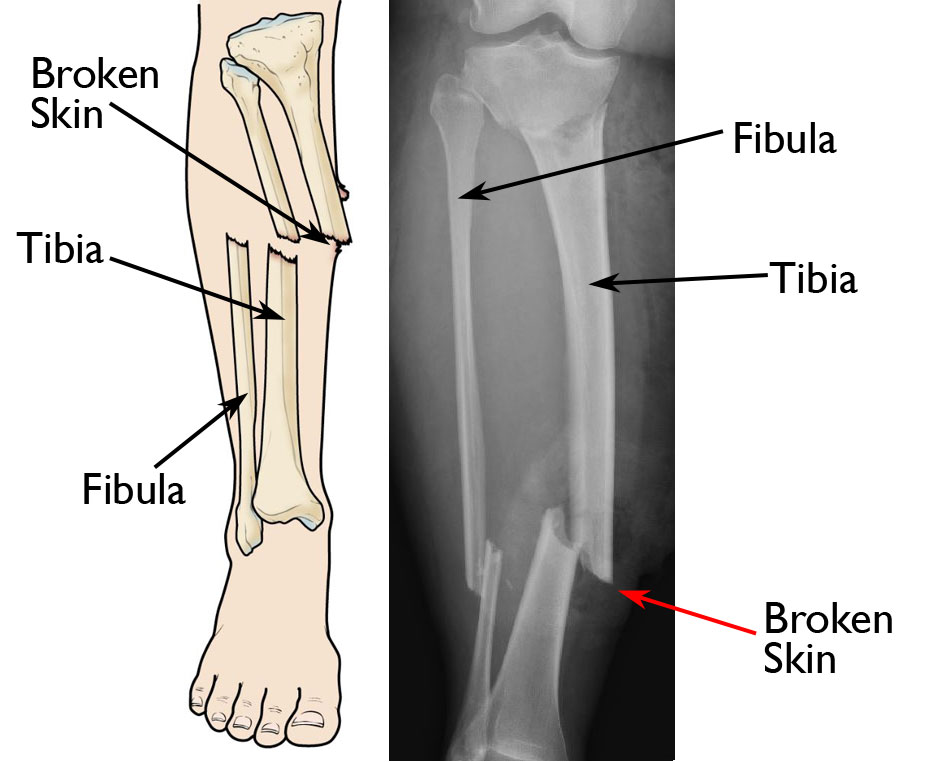

• A complicated open fracture (also known as a compound fracture); with an open fracture, there is an open wound near the fracture, usually caused by a piece of bone breaking through the skin

Illustration and X-ray show an open fracture. The broken end of the tibia (shinbone) has torn through the soft tissues and is protruding through the skin.

(Right) Reproduced from Egol KA, Gardner MJ, eds: Let's Discuss Management of Common Fractures. Rosemont, IL, American Academy of Orthopaedic Surgeons, 2016, pp. 135-152.